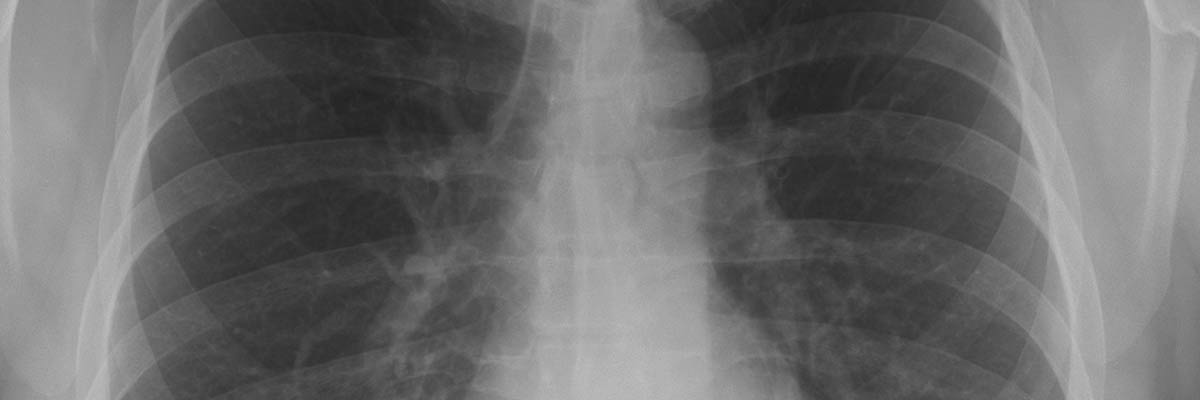

Radiography is the use of X-rays to view a non-uniformly composed material (i.e. of varying density and composition) such as the human body. A heterogeneous beam of X-rays is produced by an X-ray generator and is projected toward an object. The density and composition of each area determines how much of the ray is absorbed. The X-rays that pass through are captured behind the object by a digital detector. The detector gives a 2D representation of all the structures superimposed on each other..

X-ray exams are performed on a walk-in basis at our Fort Pierce location; except IVP exams which must be scheduled and take approximately 30 minutes.